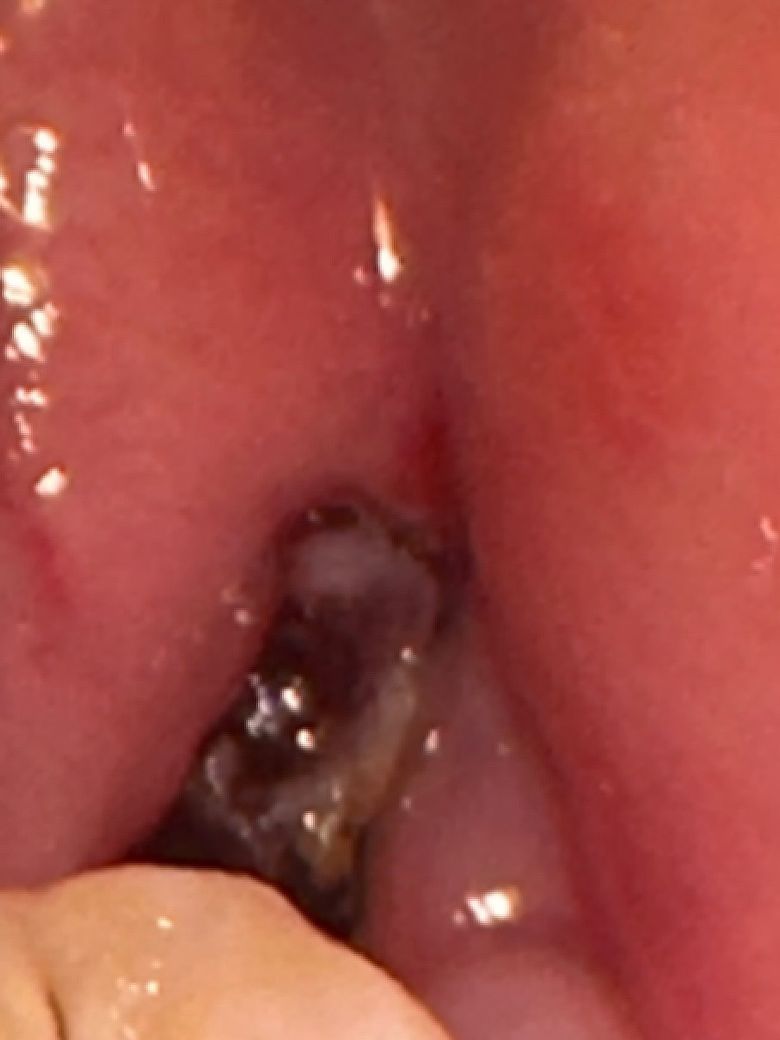

사랑니 실밥제거했는데 이거 검은색 뭔가요??

테두리로 얇게 검은색이 있는데 이거 실밥 아니겠죠? 오늘 실밥제거했는데.. 물로 쏴봐도 움직이지는 않아요 혹시 실밥이 들어간것처럼 보이시나요?